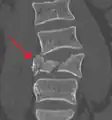

A burst fracture of L4 as seen on CT